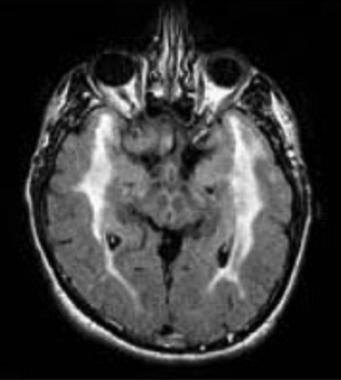

FLAIR MRI of the brain showing hyperintensities involving the temporal poles in a patient with cerebral autosomal dominant arteriopathy with subcortical infarcts and leukoencephalopathy (CADASIL). (from Mayo Clin Proc, Meschia, 2005)

Abstract Objectives: Cerebral autosomal dominant arteriopathy with subcortical infarcts and leukoencephalopathy (CADASIL) is the most common hereditary cause of vascular dementia in adults. Migraine is a major symptom of the disease. We aimed to identify clinical and demographical features of the headache associated with increased cerebral lesion burden in a cohort of CADASIL patients.

Results: Regression analysis showed that age (β = 1.266, 95%CI = [0.805, 1.726], p < 0.001), headache intensity (β = 5.143, 95%CI = [2.362, 7.924], p = 0.001) and female sex (β = 19.727, 95%CI = [8.750, 30.075], p = 0.001) were the main predictors of WMH-V.

Discussion: Age, female sex and headache intensity are associated with increased white matter lesion volume in CADASIL.